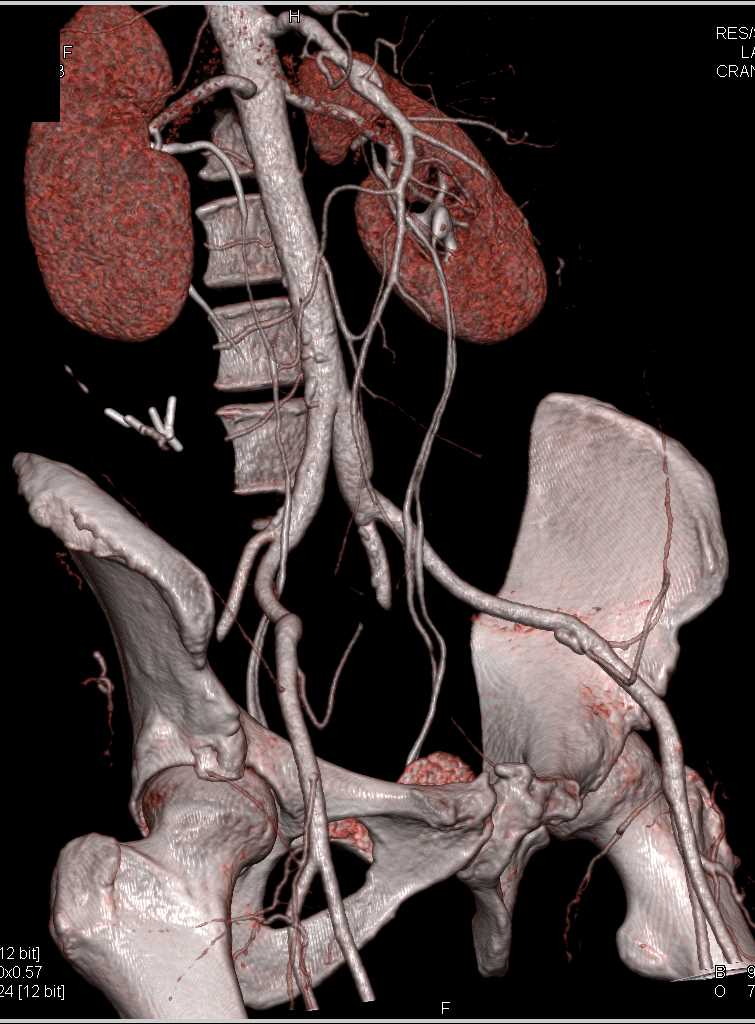

SMA Stenosis